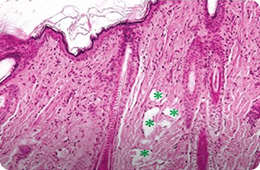

532 PS

침투깊이 : 861.15~1,229 μm

침투깊이 : 600.66~918.46 μm

출처 : A Randomized, Prospective, Split-Face Pilot Study to Evaluate the Safety and Efficacy of 532-nm and 1,064-nm

Picosecond Lasers Using a Diffractive Optical Element for Non-Ablative Skin Rejuvenation, Dermatologic Therapy, 2022